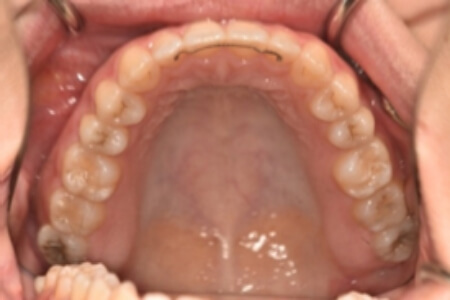

動的治療終了時

検査の結果、上下顎前歯部に空隙を伴うアングルⅠ級不正咬合と診断しました。

治療としては、非抜歯の上、マウスピース矯正装置(インビザライン)で配列を行いました。

治療期間は、1年9か月でした。